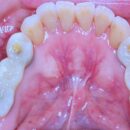

2025.11.22 下顎両側456のインプラントハイブリッド…… 下顎両側456のインプラントハイブリッドの上部構造 クリアランスが無くバイト調整に苦心しました。対合歯は弊社製作のジルコニアフルマウスです。……